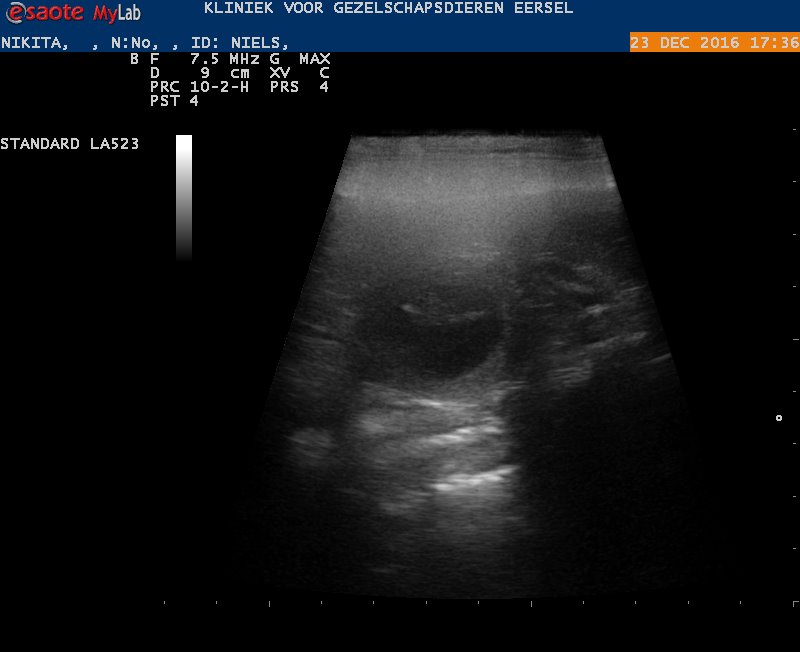

23/12/2016

Uit de echo bleek dat Nikita vom Hause Edelstein drachtig is van Giant Gino van Tousell

Meer info zie pups